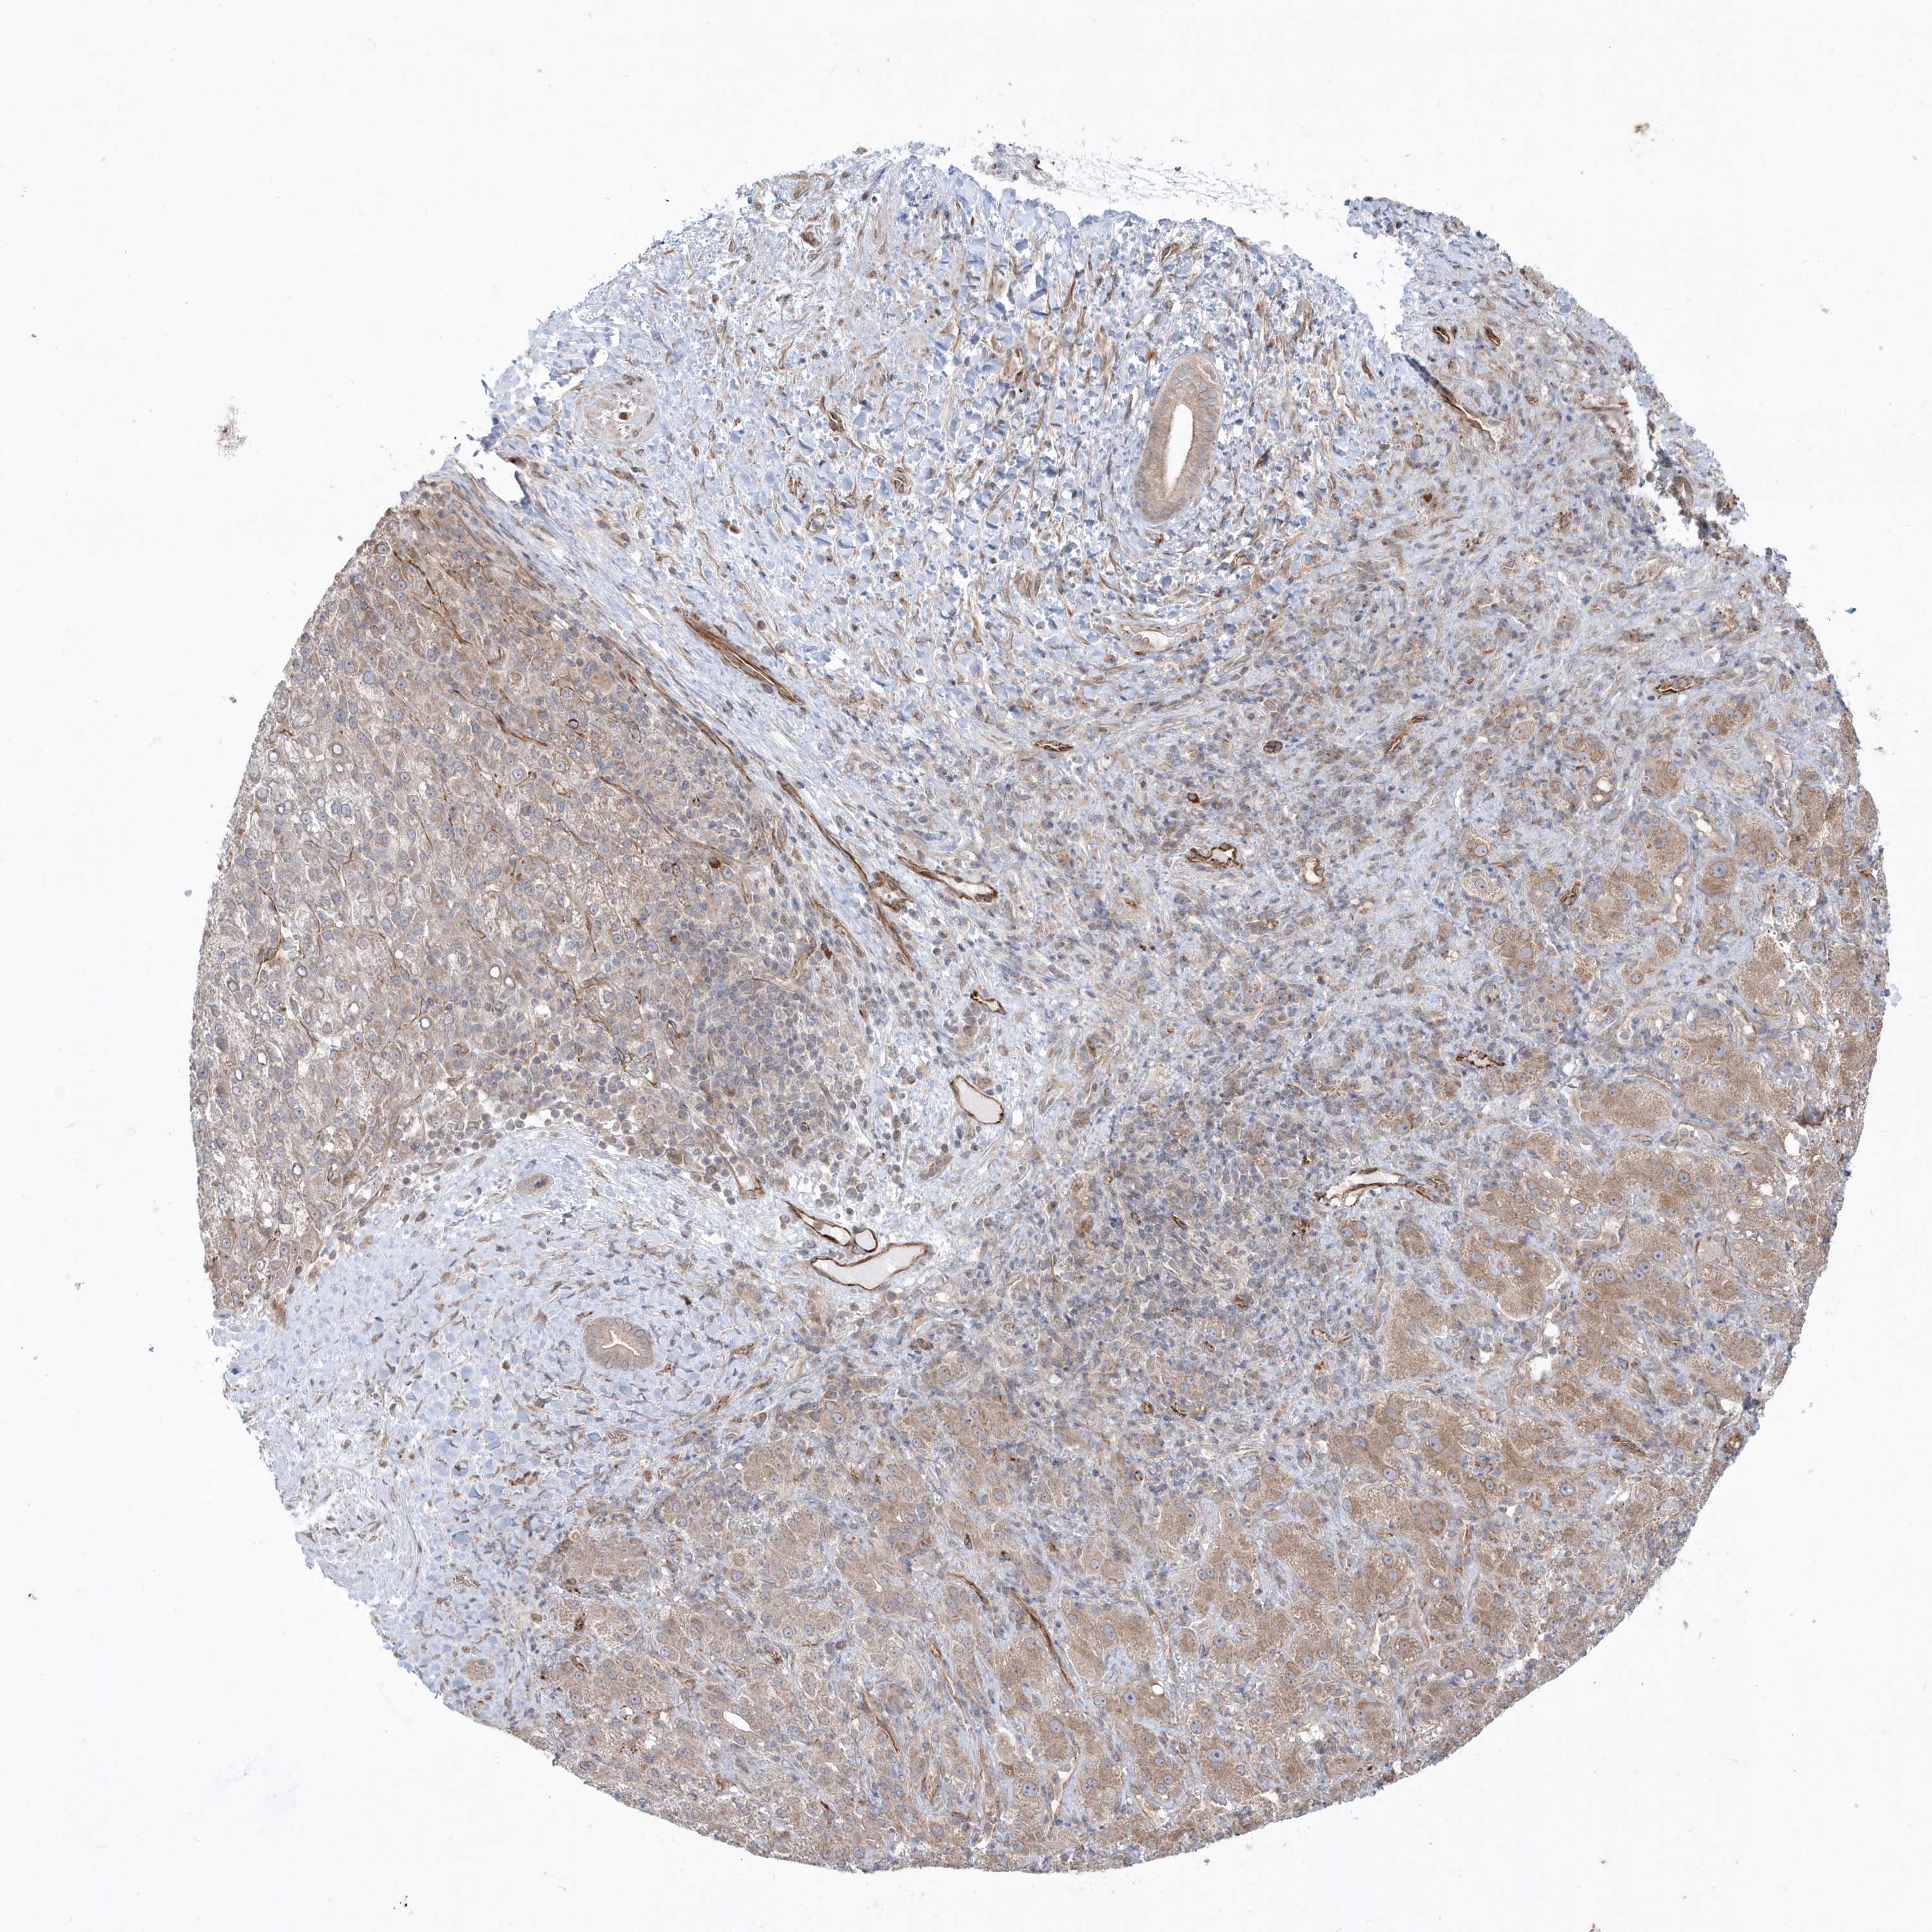

LIVER CANCER - Protein expressioni

A mouse-over function shows sample information and annotation data. Click on an image to view it in a full screen mode. Samples can be filtered based on level of antibody staining by selecting one or several of the following categories: high, medium, low and not detected. The assay and annotation is described here.

Note that samples used for immunohistochemistry by the Human Protein Atlas do not correspond to samples in the TCGA dataset.

Antibody stainingi

Antibody staining in the annotated cell types in the current human tissue is reported as not detected, low, medium, or high, based on conventional immunohistochemistry profiling in selected tissues. This score is based on the combination of the staining intensity and fraction of stained cells.

Each image is clickable and will lead to virtual microscopy that enables deeper exploration of all samples and also displays staining intensity scores, fraction scores and subcellular localization as well as patient and tissue information for each sample.

Antibody HPA036160

Staining

High

Medium

Low

Not detected

Intensity

Strong

Moderate

Weak

Negative

Quantity

>75%

75%-25%

<25%

None

Location

Nuclear

Cytoplasmic/membranous

Cytoplasmic/membranous,nuclear

Cholangiocarcinoma

Carcinoma, Hepatocellular, NOS